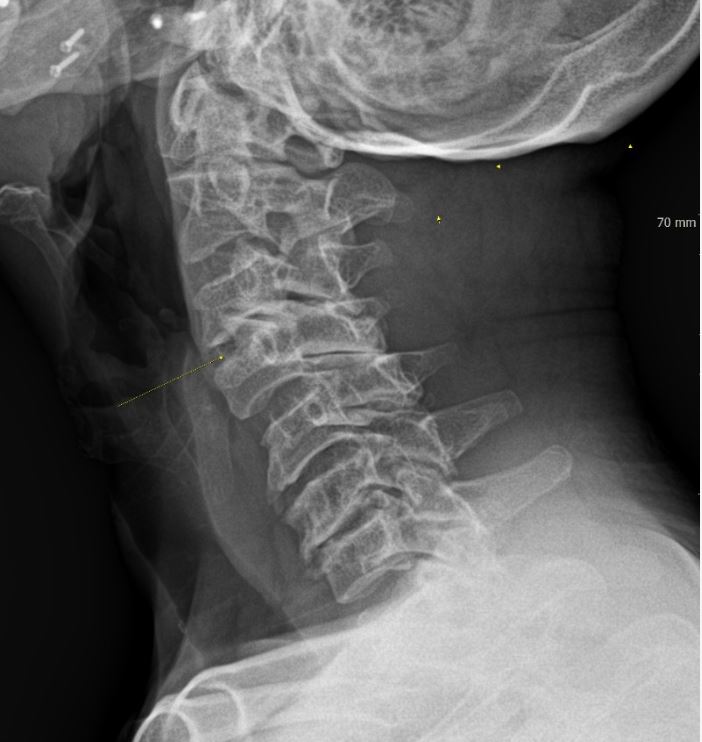

목 뼈와 뼈 사이의 디스크가 제자리에서 이탈되어 신경을 압박한 경우 혹은 뼈 조직이 비정상적으로 자라 목을 지나는 척추 신경이 눌려 통증을 인지하는 질환이예요.

종종 가슴 쪽에 통증이 나타날 수 있다고 합니다. 목에서 가슴으로 걸치는 신경이 압박되어 통증이 생성되기 때문인데 하지만 가슴통증은 다른 원인을 통하여도 일어나는 된다면가 많으니 똑바로 이해하려면 X-ray를 찍어서 확인하는 게 좋아요.